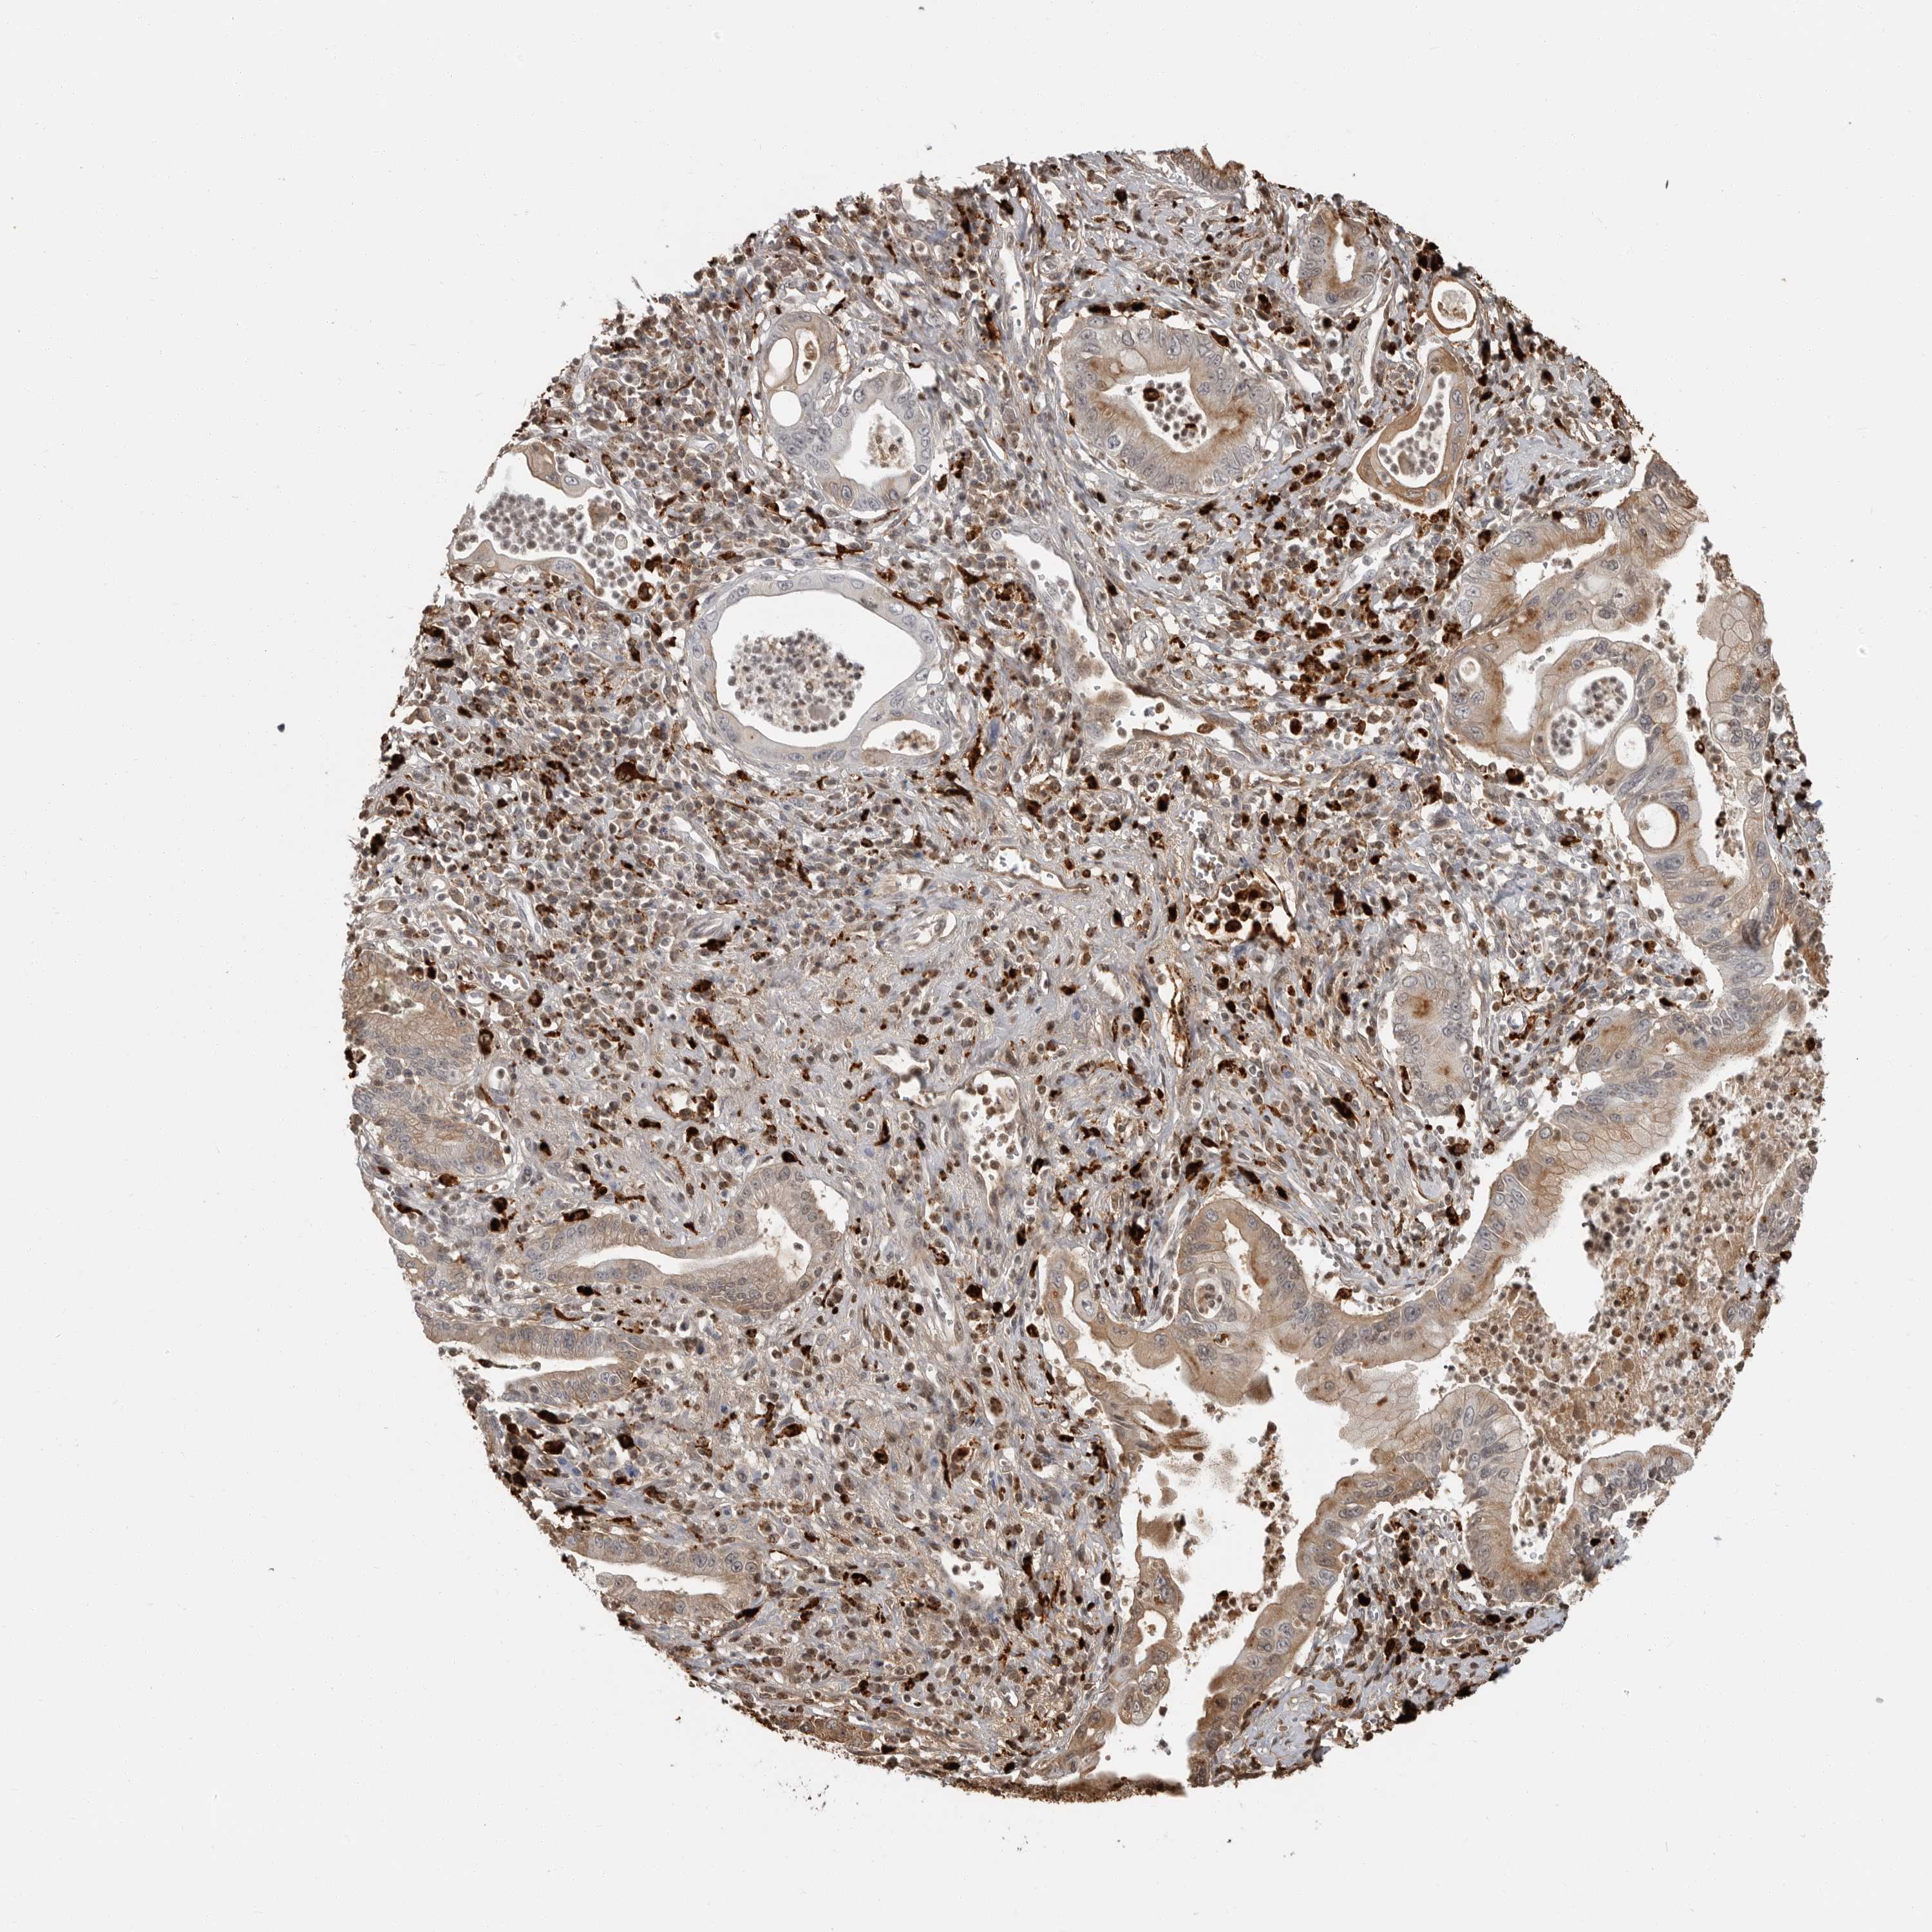

PANCREATIC CANCER - Protein expressioni

A mouse-over function shows sample information and annotation data. Click on an image to view it in a full screen mode. Samples can be filtered based on level of antibody staining by selecting one or several of the following categories: high, medium, low and not detected. The assay and annotation is described here.

Note that samples used for immunohistochemistry by the Human Protein Atlas do not correspond to samples in the TCGA dataset.

Antibody stainingi

Antibody staining in the annotated cell types in the current human tissue is reported as not detected, low, medium, or high, based on conventional immunohistochemistry profiling in selected tissues. This score is based on the combination of the staining intensity and fraction of stained cells.

Each image is clickable and will lead to virtual microscopy that enables deeper exploration of all samples and also displays staining intensity scores, fraction scores and subcellular localization as well as patient and tissue information for each sample.

Antibody HPA026650

Staining

High

Medium

Low

Not detected

Intensity

Strong

Moderate

Weak

Negative

Quantity

>75%

75%-25%

<25%

None

Location

Nuclear

Cytoplasmic/membranous

Cytoplasmic/membranous,nuclear

Adenocarcinoma, NOS